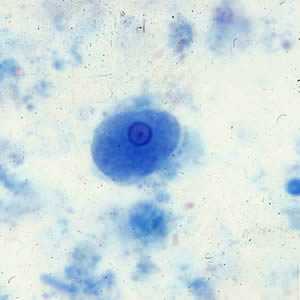

Iodamoeba buetschlii cysts in concentrated wet mounts.

Figure A: Cyst of I. buetschlii in an unstained concentrated wet mount. In these cysts, the glycogen vacuole can be seen as a large, oval refractile body.

Figure B: Cyst of I. buetschlii in an unstained concentrated wet mount. In these cysts, the glycogen vacuole can be seen as a large, oval refractile body.

Figure C: Cyst of I. buetschlii from the same specimen as seen in Figures A and B, but stained with iodine. In this cyst, the glycogen vacuole is more-easily observed as a dark-staining mass in the cyst.

Figure D: Cyst of I. buetschlii from the same specimen as seen in Figures A and B, but stained with iodine. In this cyst, the glycogen vacuole is more-easily observed as a dark-staining mass in the cyst.